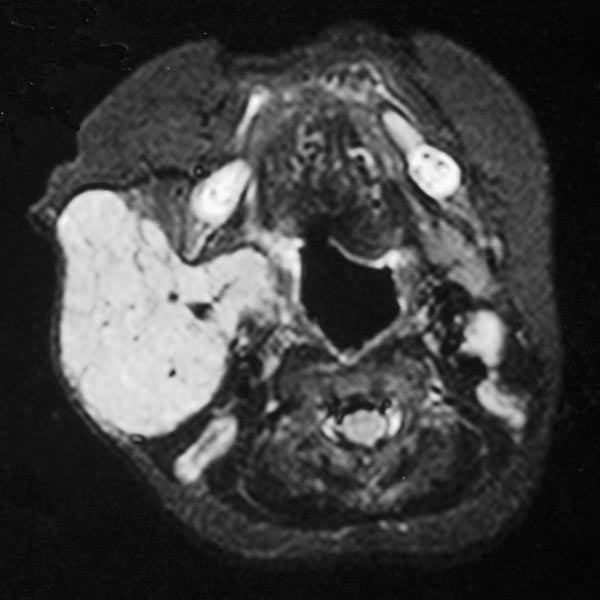

Die transversale, T1-gewichtete, native MRT des oberen Halses zeigt den subkutan gelegenen Tumor, der klar solide ist und scharf abgrenzbar zum umgebenden Gewebe. Das Mädchen ist jetzt 12 Monate alt, der Tumor hat sich nicht zurückgebildet.

Die transversale, T2-gewichtete, fettgesättigte MRT des oberen Halses zeigt den subkutan gelegenen Tumor nochmal sehr klar als hyperintense, scharf abgrenzbare Raumforderung mit zentralen Flow-voids als Zeichen der starken Perfusion. Typisches Bild eines subkutan gelegenen, infantilen Hämangioms.

Die koronare Inversion-Recovery-Sequenz (MRT) zeigt nochmals sehr gut die Ausdehnung des Hämangioms. Die Signalgebung ist isointens zum Hirngewebe. Es handelt sich klar um eine solide Raumforderung.